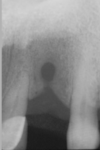

what do we see here

and is it buccal or lingual, and why:

we can tell its a mesioderm because of location (mx incisor)

Midline view, structure is covering mesial half of apex of LI, as the beam moves away from the midline the position moves to the mid of the root, more further away from midline can tell bc see the cuspid in there, now we see it covering the whole apex

As the beam moves to the right so did the structure, so SLOB, it is lingual/palatal.